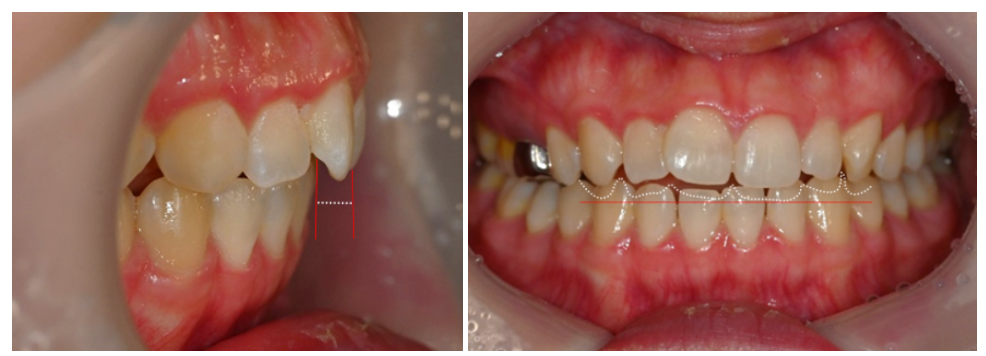

23.06.11

단, 과도한 수평피개 & 부족한 수직피개로

윗니가 아랫니를 충분히 덮지 못하는

개방교합(open bite)을 보이고 있던 상태입니다.

25.01.12

치료 후에는 어금니 뿐만 아니라 앞니 관계까지

좋아진 모습으로, 정상교합을 되찾을 수 있었습니다.